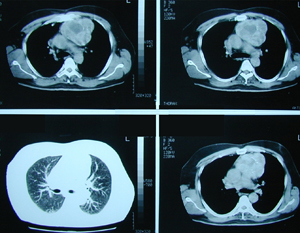

Εικόνα 3 α-δ

Αξονική τομογραφία του θώρακος. Επιβεβαιώνει τα ευρήματα της ακτινογραφίας του θώρακος. Δείχνει μάζα μαλακών μορίων, με νεκρώσεις, στο οπίσθιο μεσοθωράκιο χωρίς σημεία διήθησης παρακείμενων οργάνων.

A-B

Γ-Δ